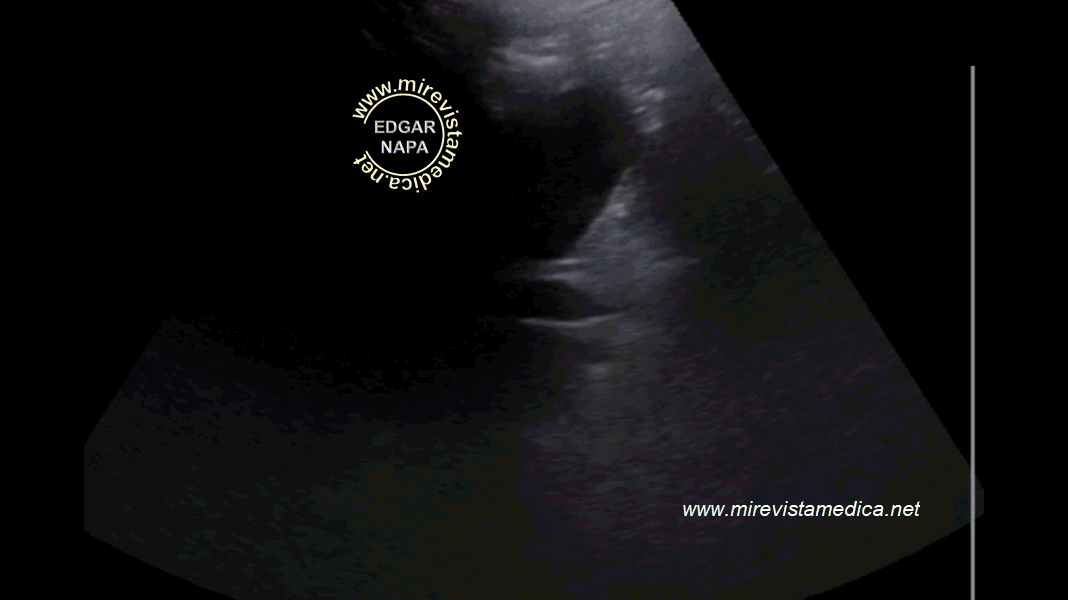

Ecografía de colédoco, incidencia sagital. Muestra características morfológicas habituales.

Ecografía de colédoco, incidencia sagital.